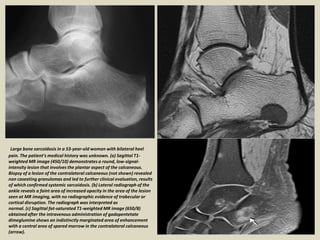

Large bone sarcoidosis in a 53-year-old woman with bilateral heel

pain. The patient’s medical history was unknown. (a) Sagittal T1-

weighted MR image (450/10) demonstrates a round, low-signal-

intensity lesion that involves the plantar aspect of the calcaneous.

Biopsy of a lesion of the contralateral calcaneous (not shown) revealed

non caseating granulomas and led to further clinical evaluation, results

of which confirmed systemic sarcoidosis. (b) Lateral radiograph of the

ankle reveals a faint area of increased opacity in the area of the lesion

seen at MR imaging, with no radiographic evidence of trabecular or

cortical disruption. The radiograph was interpreted as

normal. (c) Sagittal fat-saturated T1-weighted MR image (650/8)

obtained after the intravenous administration of gadopentetate

dimeglumine shows an indistinctly marginated area of enhancement

with a central area of spared marrow in the contralateral calcaneous

(arrow).